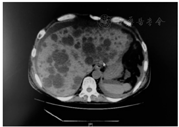

6个月前,受者以"高热伴左侧腰痛、恶心呕吐6日"入院,体温最高39.5 ℃,给予哌拉西林钠/他唑巴坦钠4.5 g/d经验性抗感染治疗,血培养提示大肠埃希菌(+),腹部CT检查(图1)显示,左肾明显增大,左肾实质内可见多发大小不等的类圆形低密度灶,内可见散在结节状致密高密度灶,考虑左侧多囊肾囊内破裂继发感染,调整抗生素为美罗培南2 g/d,并行左肾切除术,术后受者体温恢复正常,血肌酐稳定(波动在129~156 μmol/L)。